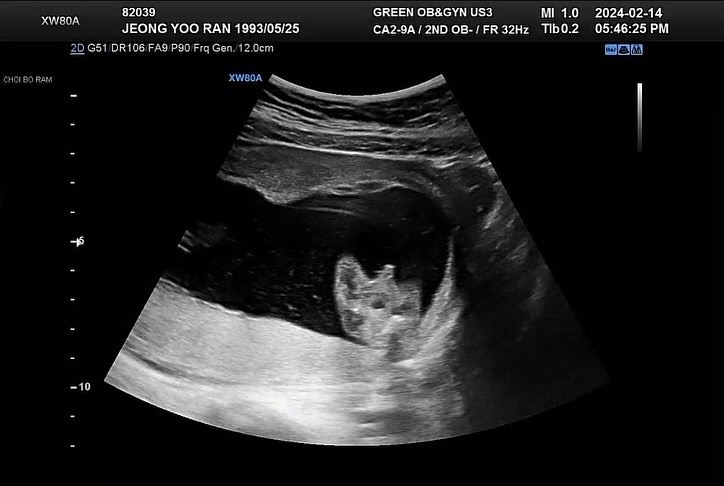

16주 5일에 간 병원에서 드디어 성별확인했어요 딸을 원했지만 왼쪽으로 봐도 오른쪽으로 봐도 가운데 우뚝 선 산이 보이네요 ㅋㅋㅋㅋㅋㅋㅋ 초음파에서 안보이면 어떡하나 걱정한게 무색하게 다리를 아주 쫙 벌리고 보여줘서 저도 남편도 의사쌤도 보자마자 웃었네요 ㅋㅋㅋ 이제 진짜 아들맘인가봐요 ㅠㅠㅠ ㅋㅋㅋ